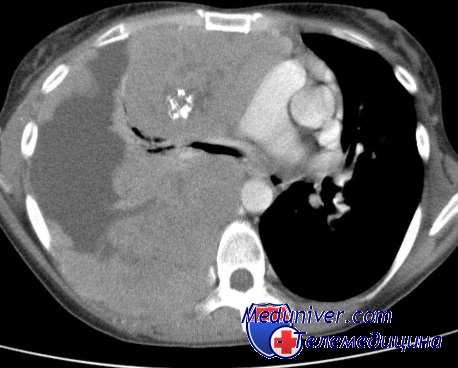

Рис. 1

Гранулематозный периодонтит

16-го зуба

Рис. 4

Гранулирующий периодонтит

12-го зуба

Рис. 2

37-го зуба

Рис. 5

11-го зуба

Рис. 3

Острый пульпит 36-го зуба

Рис. 6

21-го зуба

Рис. 7

Одним из достоинств композитных материалов, заявляемых фирмами-производителями, является простота в использовании в связи с отсутствием необходимости наложения изолирующих материалов в проекции пульпы зуба. Это положение взято на вооружение практикующими врачами, так как позволяет экономить время врача, средства клиники и давать лучшие эстетические результаты, особенно в больших полостях 3-го и 5-го классов, в сравнении с комбинированным применением прокладочного материала и композита. Действительно, применение изолирующего прокладочного материала заставляет врача считаться с его оптическими свойствами (цветом, прозрачностью, занимаемым объемом) и каким-то образом вносить коррективы в выбор цвета и опаковости используемого композита. Все это существенно усложняет и удлиняет работу врача, поэтому фирмы-производители рекомендуют применять адгезивную систему композитов непосредственно на дентин, утверждая, что образующийся гибридный слой и служит прокладкой, достаточно хорошо защищающей пульпу от действия пломбы. Однако наши многолетние клинические наблюдения показали, что отсутствие изоляции дентина при использовании адгезивных систем и фотокомпозитов при лечении витальных зубов в течение 6–12 месяцев приводит к некрозу пульпы и дальнейшему развитию гранулирующего или гранулематозного периодонтита. Особенностью течения этого процесса является отсутствие или слабая выраженность симптомов, предшествующих некрозу пульпы.

На наш взгляд, даже правильная работа с адгезивной системой (хорошая изоляция рабочего поля коффердамом, соблюдение вре-менного режима нанесения компонентов) не всегда является залогом успеха лечения. Мы предполагаем, что за 15–20 секунд экспозиции гидрофильные компоненты адгезива успевают достичь пульпы даже при неглубоких кариозных полостях и оказать свое токсическое воздействие. Дальнейшее отсвечивание приводит к полимеризации адгезива и образованию гибридного слоя на поверхности дентина. В литературе практически полностью отсутствуют данные о морфологическом состоянии клеток пульпы после применения адгезивов. Исследования, проведенные на нашей кафедре (В. В. Патюков, 2000) на крысах, свидетельствуют о тканевой инертности полимеризованной порции композита и выраженном токсическом действии неполимеризованного и недополимеризованного композита, причем наиболее выраженный некроз тканей наблюдается именно при действии неполимеризованного адгезива. Рентгенограммы, приведенные ниже, иллюстрируют наши клинические наблюдения.